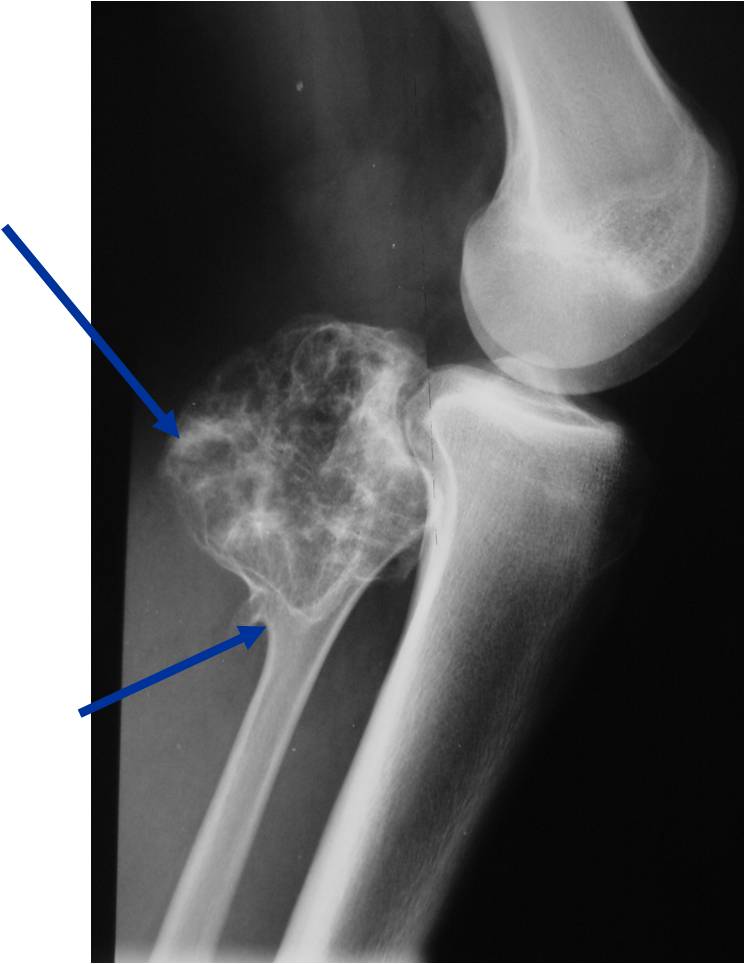

Radiographic Presentation

Plain X-rays:

- Projects from bone with narrow (pedunculated) to broad (sessile) stalk

- Corticomedullary continuity: Medullary bone continuous with that of osteochondroma and cortex blends with that of osteochondroma

- Calcification in cartilaginous cap (“Ring and Arc” and stippled calcifications)

- Lobular growth pattern

- Long bones: arise from metaphysis, grows away from epiphysis toward diaphysis,